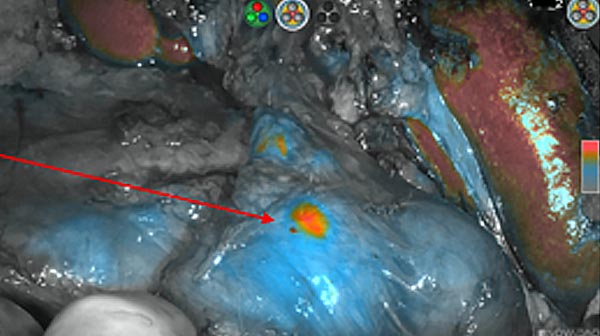

Intraoperative fluorescence imaging of the pancreas part that contains tumor

The tumor area light up fluorescently and so does a lymph node (LN; red circle) that is located on top of the tumor area. We can also see some lymphatic ducts (green circle).

After removal of the pancreas tumor fluorescence imaging was performed to check that there was no residual fluorescence left in the wound bed. A little bit of background fluorescence was found in the intestine.